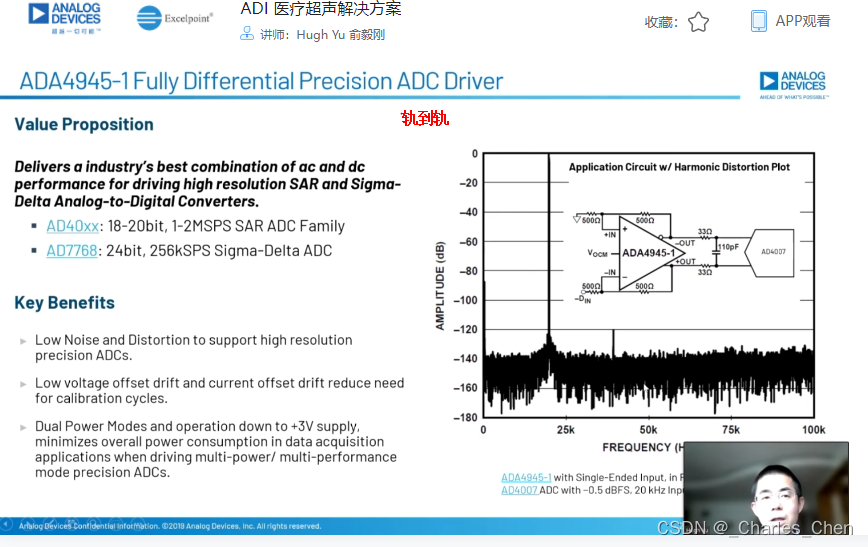

抗混叠滤波器(AAF)和ADC

抗混叠滤波器AAF置于接收通道,用于滤除高频噪声和超出正常最大成像频率范围的信号,防止这些信号通过ADC转换混叠至基带。设计中大多采用可调节的AAF,为了抑制混叠并保证信号的时域响应,滤波器需要对第一奈奎斯特频率以外的信号进行衰减。因此,常常使用巴特沃斯滤波器或更高阶的贝塞尔滤波器。

典型应用中采用12位ADC,采样率通常在40Msps至60Msps之间。ADC提供必要的瞬态动态响应范围,同时具有适当的成本和功耗。在设计得当的接收器中,ADC会限制接收通道的瞬态SNR。如上所述,性能差的VGA会限制整个接收通道的SNR指标。

CWD接收机通常使用两种方法处理CWD信号。第一种方法是高性能超声系统在LNA输出端提取接收到的CWD信号。本振频率等于发送频率的混频器对信号进行波束成形,再混频至基带进行处理。I/Q本振信号可以逐通道调整相位,对接收到的CWD信号相位进行偏移。混频器输出相叠加,经带通滤波器,最后进入ADC进行采样。采样得到的基带波束信号处于音频范围(100Hz至50kHz),采用工作在音频频率范围的ADC对I和Q CWD信号进行数字化。这些ADC需要出色的动态范围,以便处理运动组织产生的较大的低频多普勒信号和血液产生的微弱信号。

另一种方法是使用延迟线接收CWD信号,该方法常用于低成本设备。在此方法中,信号还是从LNA输出提取,然后转化成电流信号。通过一个交叉开关对相同相位的通道进行叠加,产生8至16路独立输出,具体由接收波束成形器决定。延迟线产生延迟,并将这些信号求和构成一路波束成形RF信号,然后利用一个本振频率等于发送频率的I/Q混频器将信号混频至基带,然后将基带音频信号滤波后,转换至数字形式。